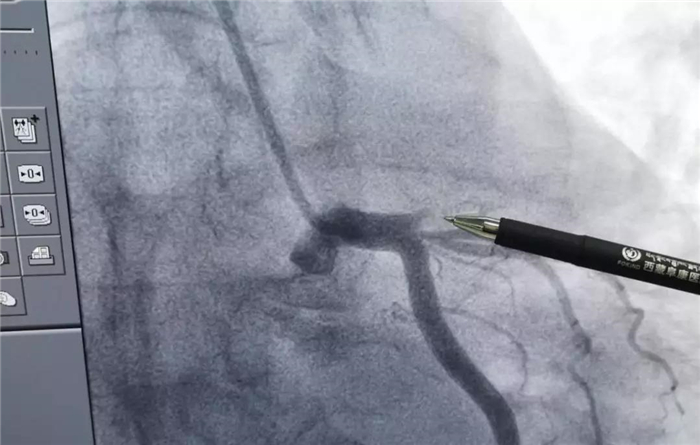

血運(yùn)重建手術(shù)后

手術(shù)中,心血管病介入團(tuán)隊(duì)將患者的血栓抽出,植入支架,再經(jīng)心血管內(nèi)超聲(IVUS)檢查顯示:患者支架貼壁良好,無夾層、血腫、血栓影,前向血流TIMI3級(jí)。經(jīng)過45分鐘,手術(shù)順利完成,患者胸痛、胸悶癥狀消失,安全返回病房,患者及家屬均對(duì)這次手術(shù)給予了肯定。